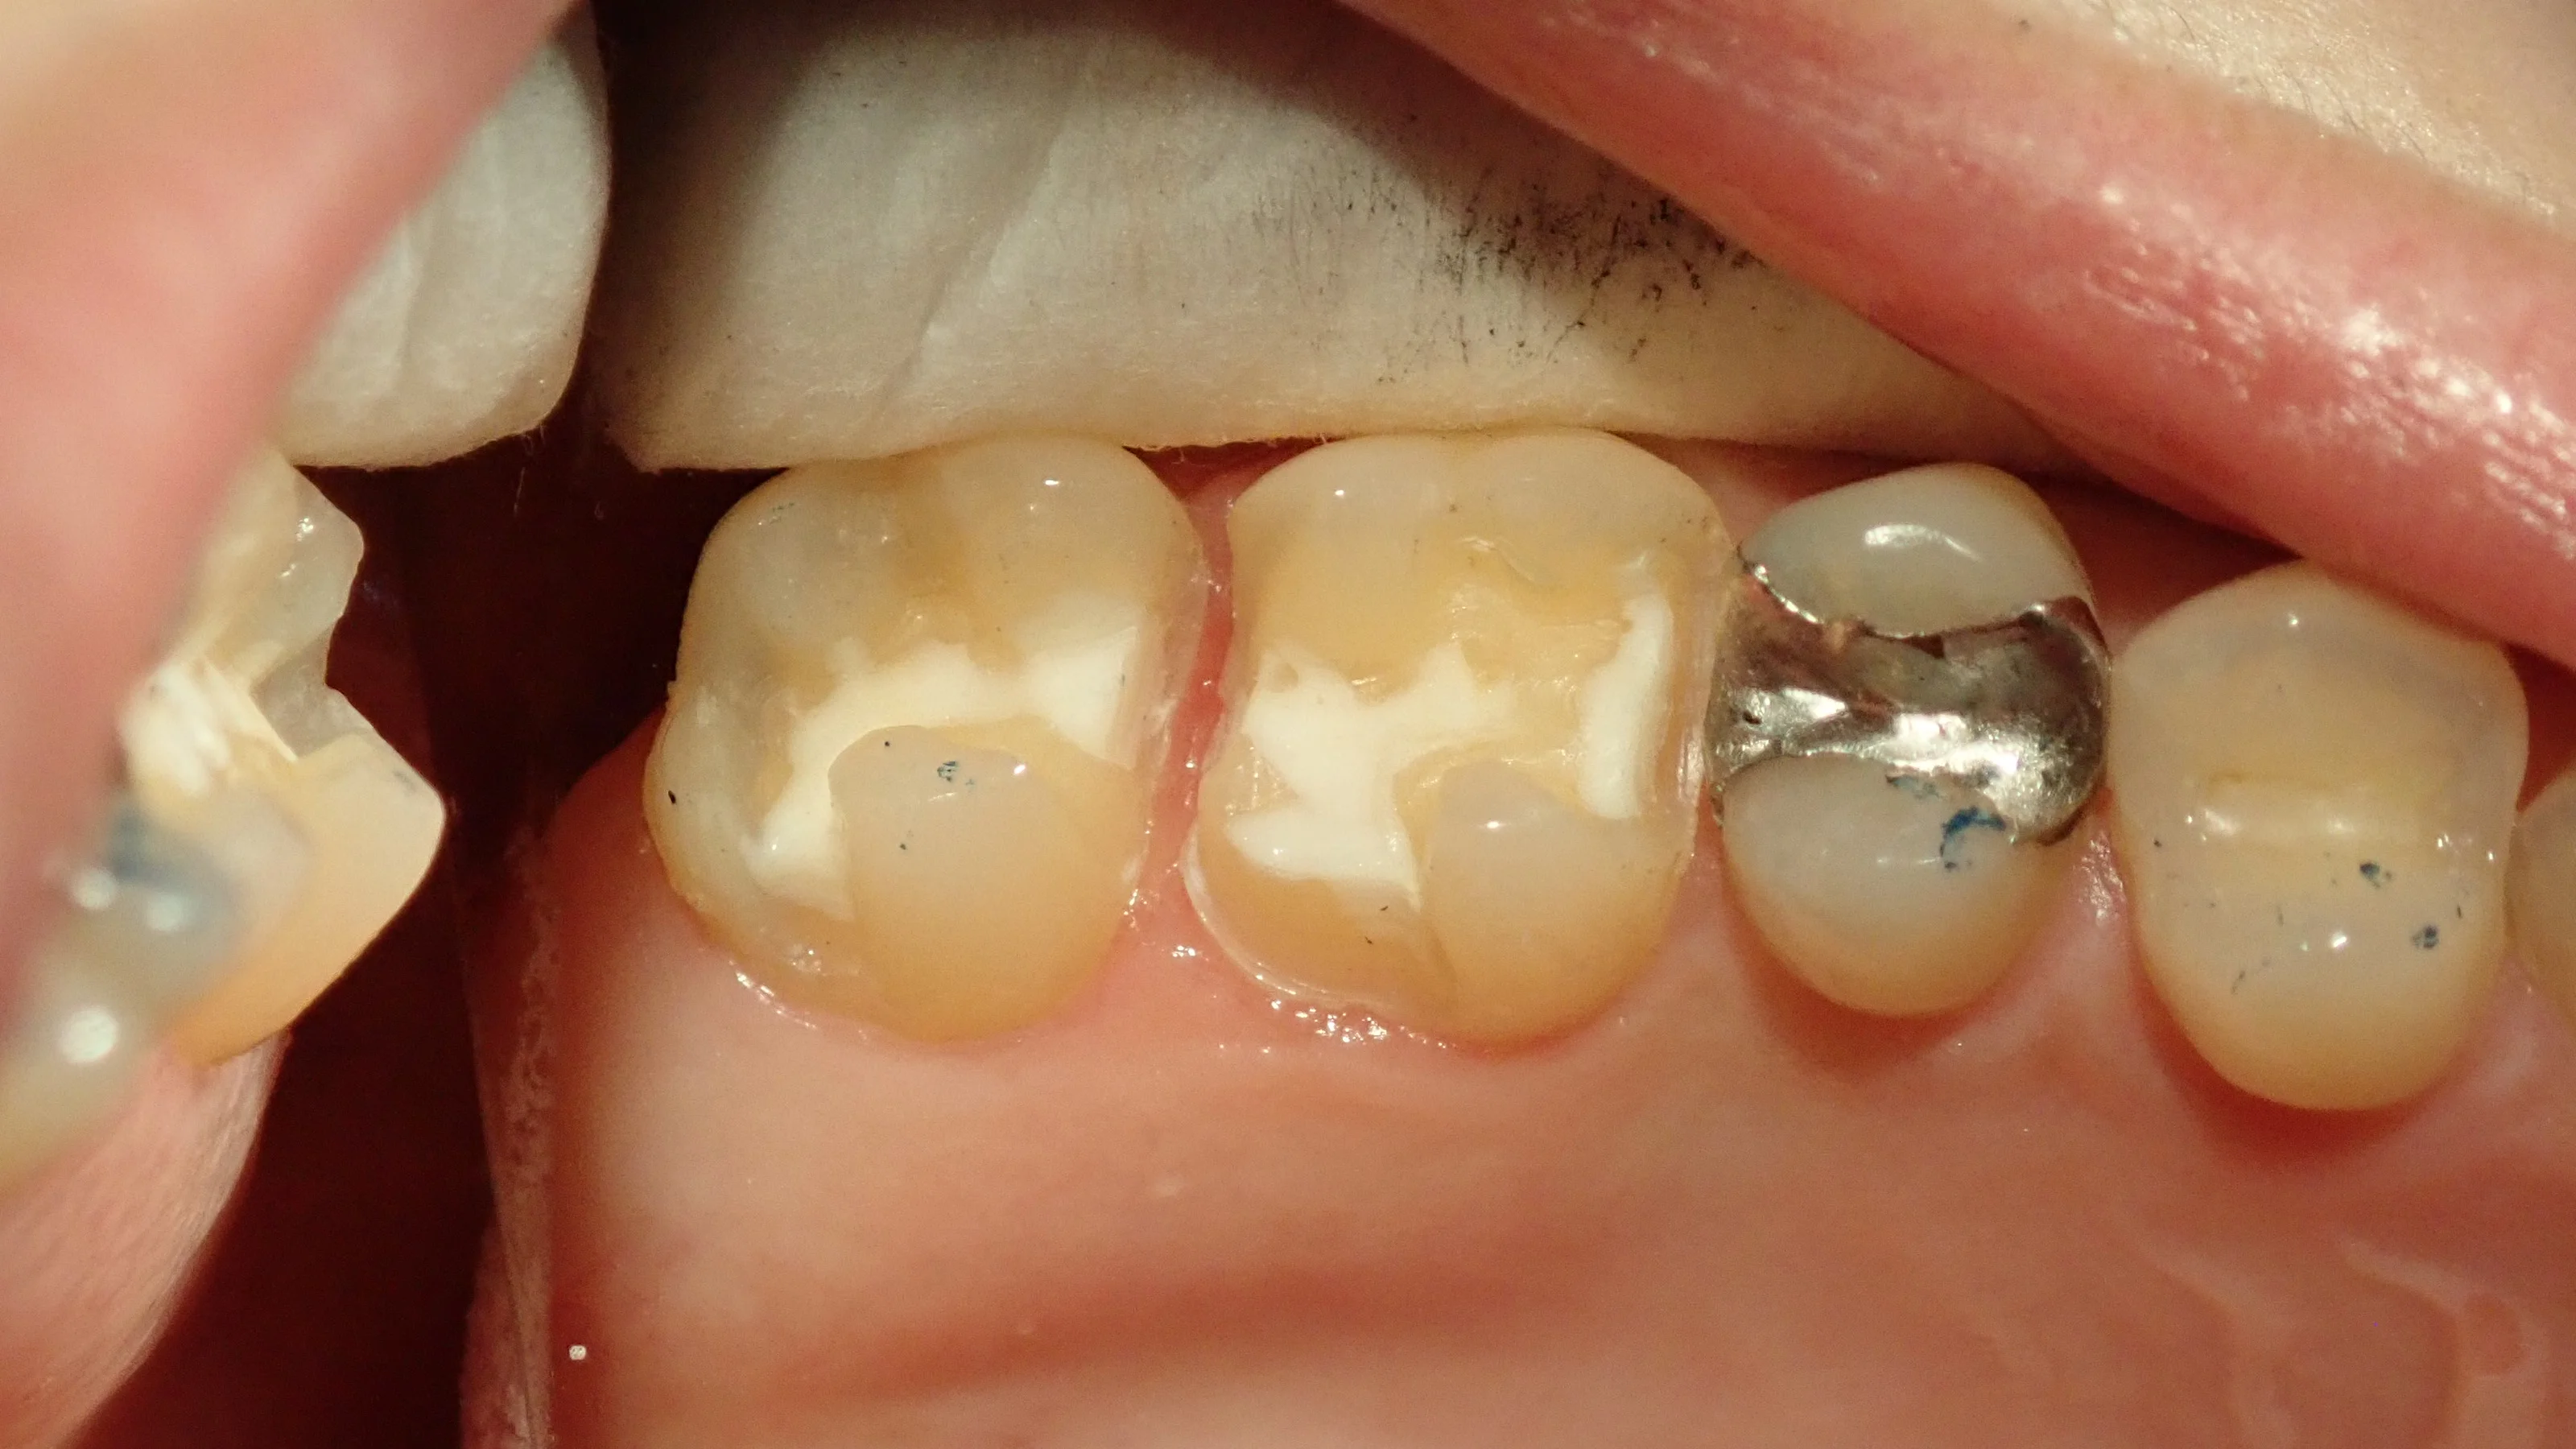

模型の写真をアップします。

こういった形です。

グレーのところはセメントラインと言います。

セメントが入る箇所を予め作成してから金属を作らないとセメントが綺麗に入りませんからね。

この形作りのときに面をガタガタにてしまったりすると更に形が複雑になってしまいます。

その結果、適合の悪い金属しか出来なくなってしまうのです。

余りに形が悪いと、技工士さんが作りやすくするために、ピンクとか白い材料で段差をなくすという一手間が必要になってしまいます。